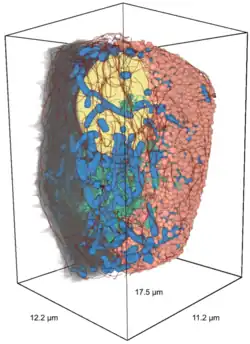

Bètacellen hebben een gemiddelde diameter van 10 micrometer (μm) en een lengte van ~17 μm. Het totale membraanoppervlak van een bètacel werd geschat op ≈973 vierkante micrometer (µm²). Het berekende volume van een bètacel zou gemiddeld ≈1430 kubieke micrometer (µm³) zijn.[7][8]

Het berekende volume van de muizencelkern ligt tussen de 110 en 168 kubieke micrometer (µm), wat 14-16% van het totale celvolume vertegenwoordigt.[7] [8]

Het golgicomplex van de bètacel is verantwoordelijk voor de modificatie en distributie van eiwitten (pro-insuline) die in het endoplasmatisch reticulum zijn gesynthetiseerd en omringt deze met een membraan, waardoor vesikels met insulinekorrels ontstaan die buiten de cel worden uitgescheiden. Het volume van het golgicomplex van de bètacel bedraagt tussen de 18 en 22 µm3, wat 0,90 tot 2,20% van het celvolume is.[8]